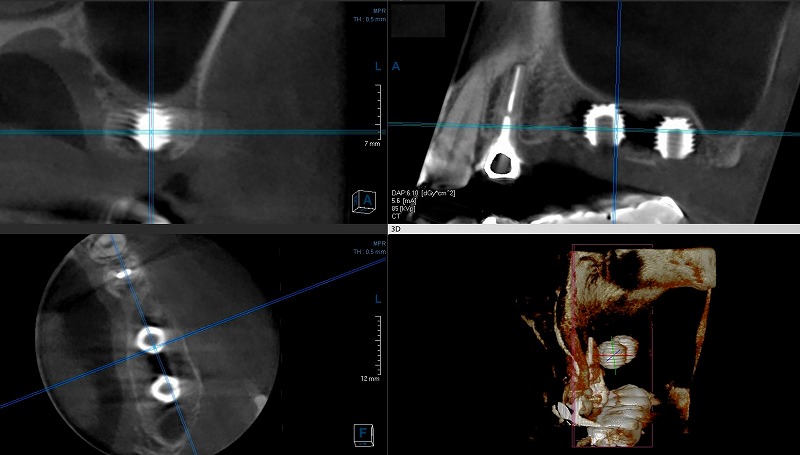

ショートインプラント症例

左の上の歯が3本なくて、しかも骨の高さが足りませんでした。そこで、造骨する事無く後ろ側に二本のショートインプラントをいれました。

そんな、症例のCT画像です。

骨が無い場合は、骨を作る事も有りますが、ショートインプラントと言って短い物を使うと造骨の必要もなくなります。